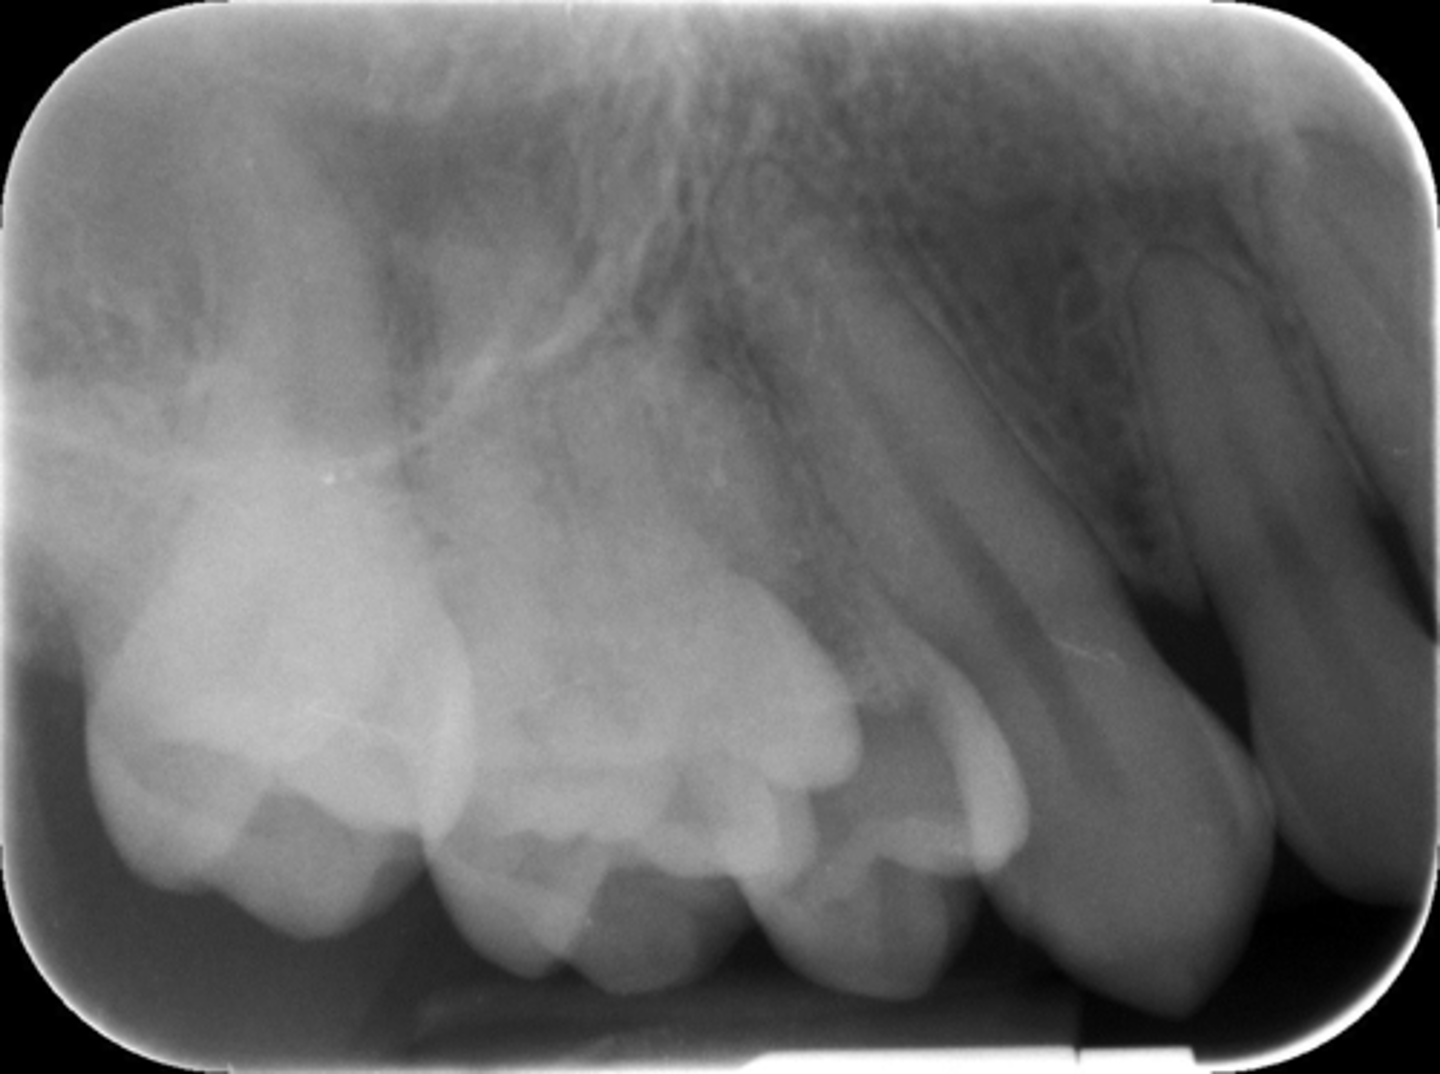

What is this projection of?

Premolars projection

Wrong film direction, backwards, positive angulation, wrong film size, no open contacts

What is this error?